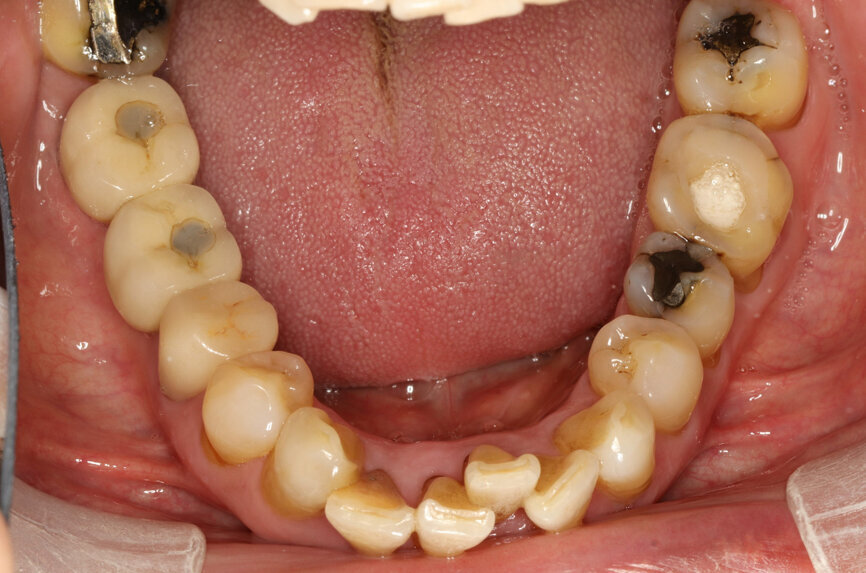

Fig. 2: Panoramic radiograph.

After careful assessment of the patient’s anatomical condition through a panoramic radiograph and CBCT scan (Figs. 1–3), it was possible to verify ideal interradicular bone availability, allowing the following treatment plan:

A 68-year-old male patient, a non-smoker, presented with controlled Type 2 diabetes. He had undergone previous dental implant treatments with positive results in the past. The patient presented to the office with tooth #36 in a non-restorable condition with indication for extraction. He requested a dental implant as the treatment choice.